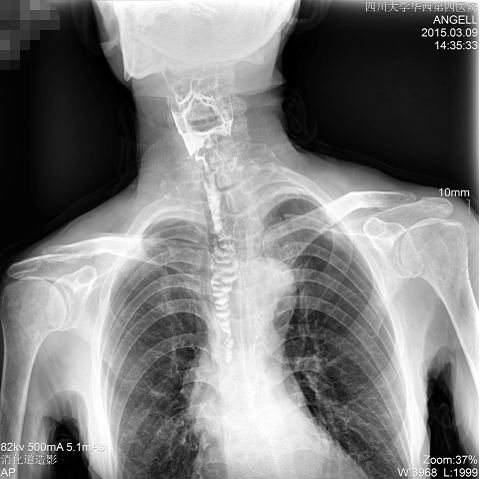

如下圖所示:該患者因吞咽時(shí)感到很難受,進(jìn)食時(shí)也經(jīng)常咳嗽故就醫(yī)診斷。華西醫(yī)院醫(yī)生使用動態(tài)DR為病人進(jìn)行消化道造影診斷,要求他吞鋇后發(fā)現(xiàn),食道各段通過順利,形態(tài)規(guī)則,雙側(cè)梨狀窩不對稱左側(cè)稍淺,多次吞咽動作后,仍見鋇劑滯留,并見鋇劑進(jìn)入氣管,屬于會厭征陽性。會厭功能紊亂,鋇劑進(jìn)入了氣管。

圖為正位:通過動態(tài)影像可以清楚看到鋇劑進(jìn)入了支氣管道且雙側(cè)梨狀窩不對稱